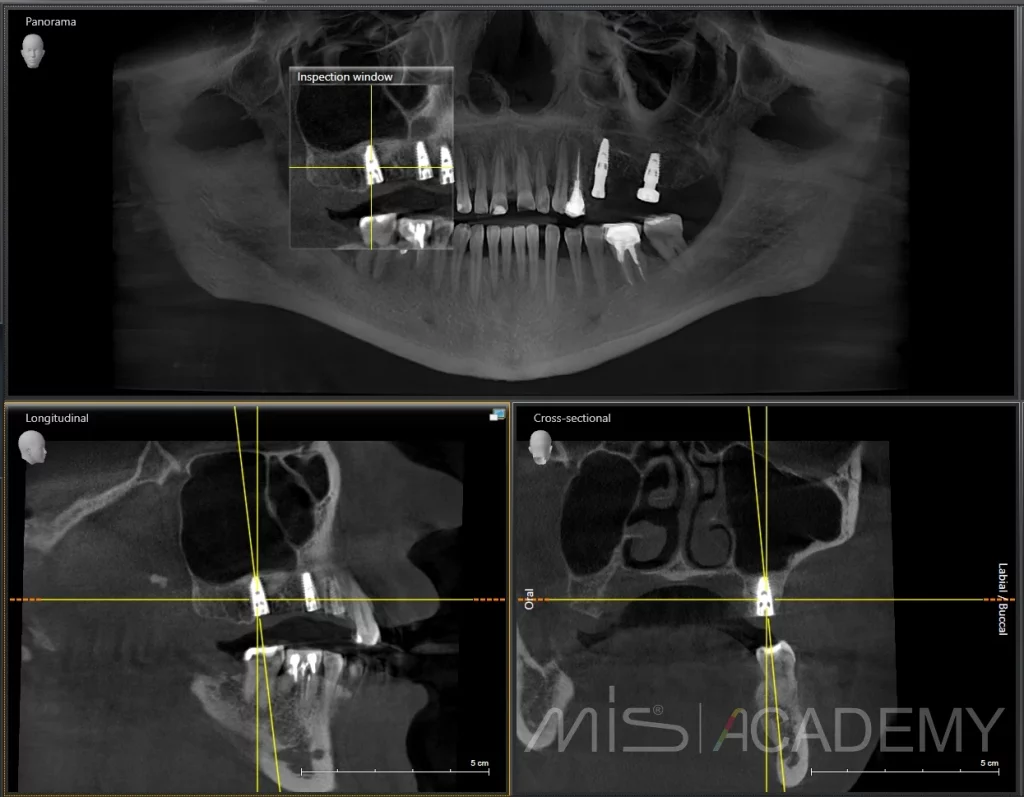

Клинический случай установки имплантатов с небольшим открытым синус-лифтингом.

— Сделали одномоментно синус-лифтинг и установку имплантатов МИС С1 под заглушку.